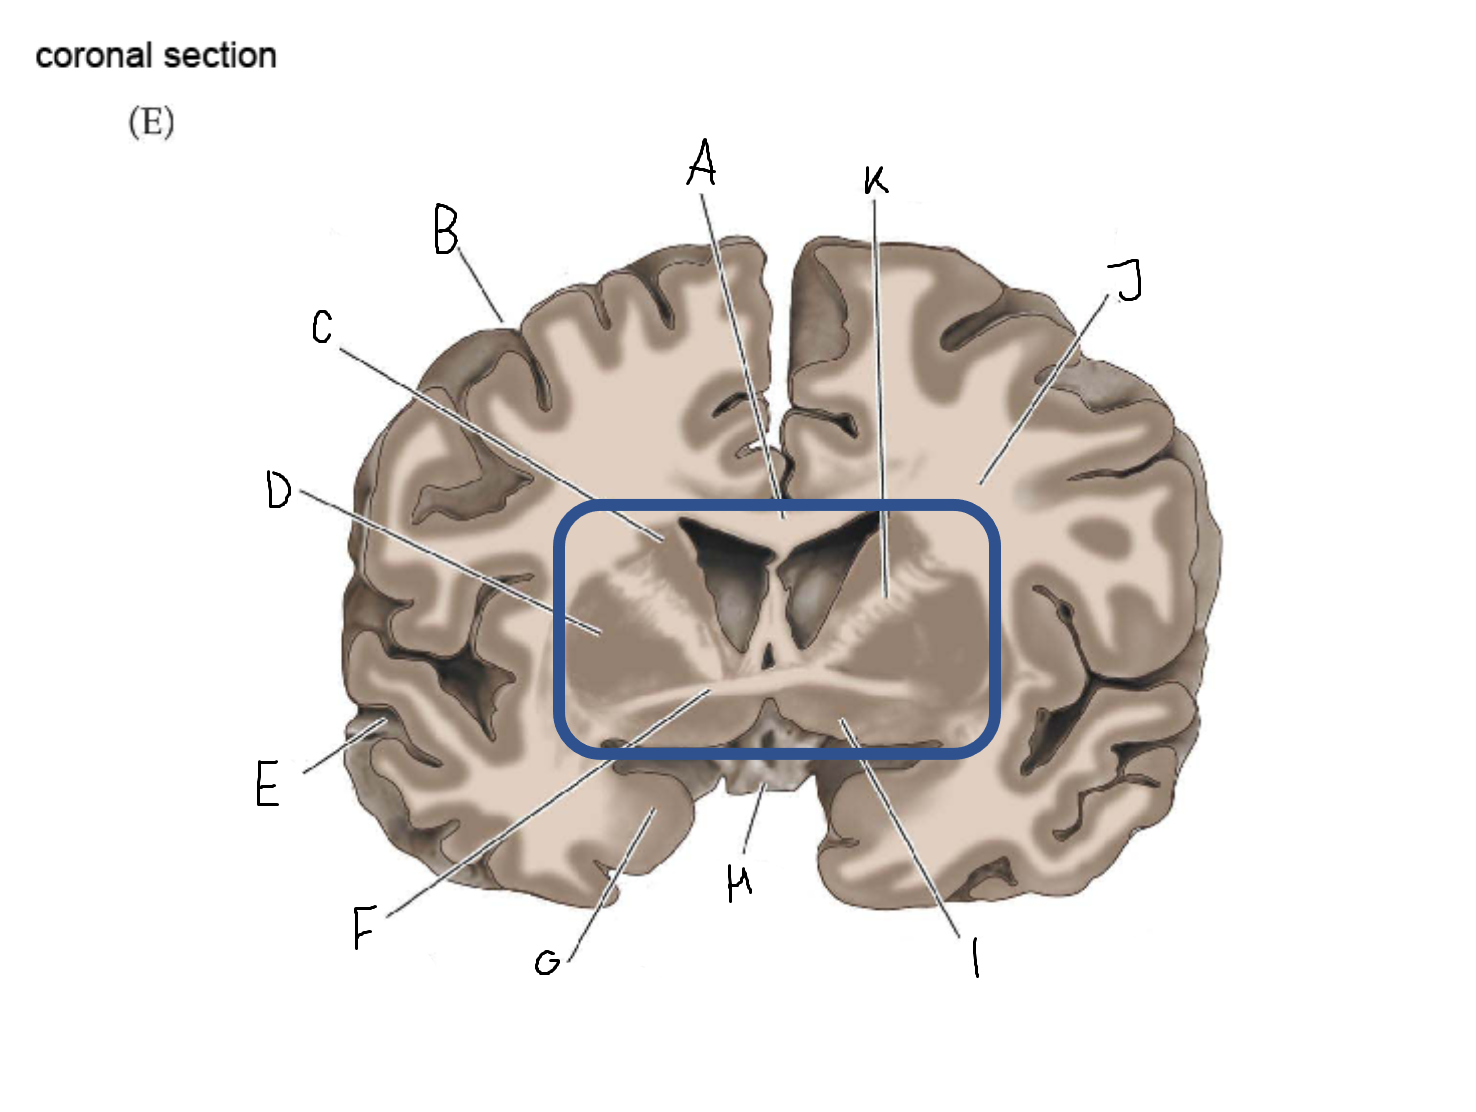

A

head of caudate nucleus

C

putamen

D

external segment of globus pallidus

E

internal segment of globus pallidus

F

third ventricle

G

thalamus

A

corpus callosum

B

cerebral cortex

C

caudate

D

putamen

F

anterior commissure

G

amygdala

H

optic chiasm

I

basal forebrain nuclei

K